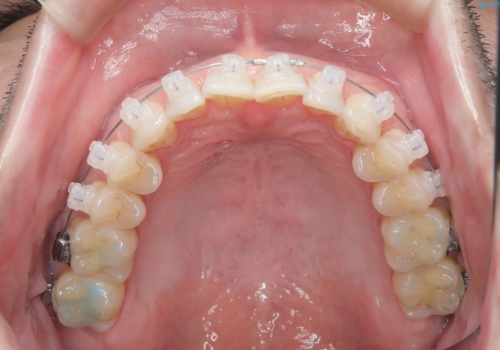

定期健診で歯並びを相談 セラミックブラケットでのワイヤー矯正例

- インシグニア デイモンクリア

- 治療計画

- 定期健診の際に、下顎前歯のガタつきが年々悪化しているとの相談を患者様より頂戴しました。下顎前歯の叢生(ガタつき)程度や患者様の希望もあり、非抜歯でも無理のない範囲と考えワイヤー矯正にて治療計画を立案しました。着色の少ないセラミックブラケットを使用しています。

日常生活において歯は1本ずつ独立した動きをします。コンタクト部分(隣の歯と触れ合っている接触点のこと)が擦り減っていくことで、一般に歯は少しずつ前歯の方に傾斜していきます。要因は様々ですが、このことにより特に前歯において叢生(ガタつき)の程度が大きくなっていくことが考えられます。他にも、歯周組織の状態も歯の配列に大きな影響を与えます。ワイヤー矯正中はブラッシングの難易度が上がりますが、磨きにくい部分は毎回診療中に患者様と一緒に鏡を見ながら確認しました。